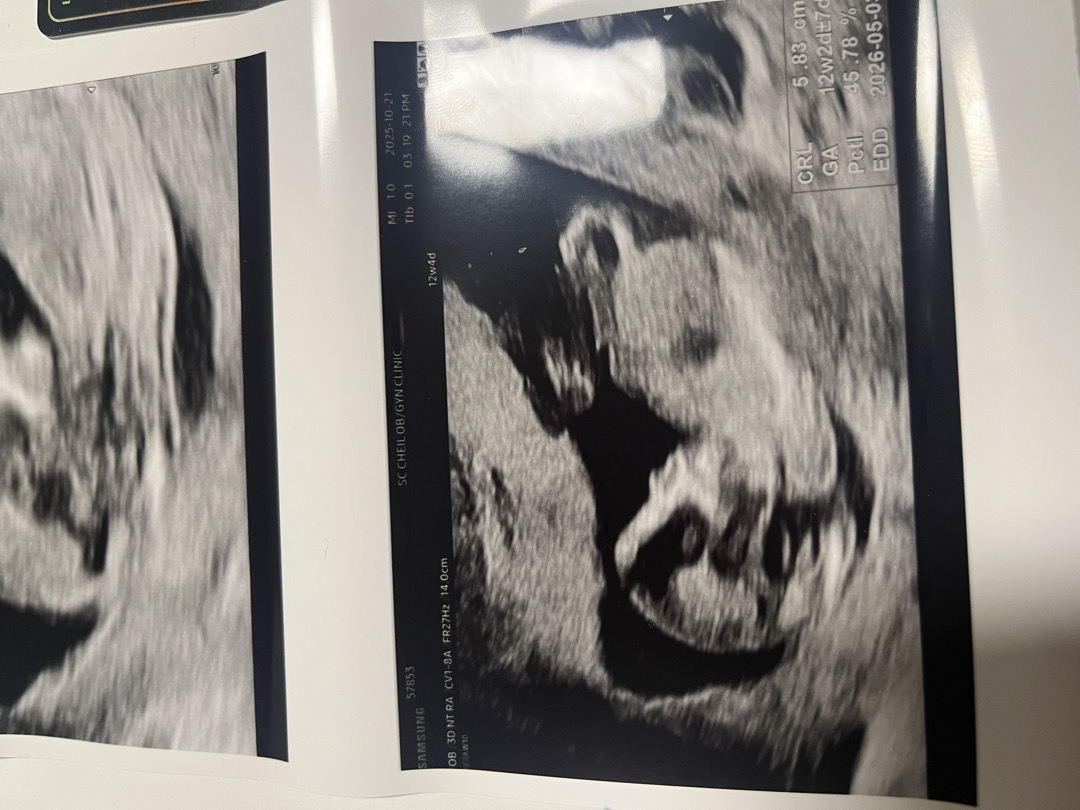

12주차 각도법 봐주세용(고난이도)

오늘 12주차 초음파 봤는데 각도법 예측이 너무 어렵네요ㅜㅜ아들일까요 딸일까요?